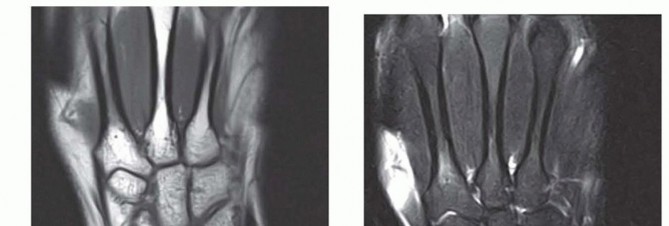

Advanced imaging, specifically Magnetic Resonance Imaging (MRI), is indispensable. We utilize high-resolution 3T MRI, often with intra-articular gadolinium (MR arthrography), to delineate the exact morphology of the TFCC tear and assess the integrity of the intrinsic carpal ligaments.

FIG 3 • B,C. T1 and T2-weighted MRIs of a wrist with ulnar abutment. Note the hyperintense signal on the T2 sequence at the ulnar proximal lunate, indicative of intraosseous edema and microtrabecular trauma secondary to chronic impaction.

The MRI allows us to map the extent of the central perforation. If the tear is small, we know we will need to enlarge it during the débridement phase to gain adequate access to the ulnar dome for the subsequent wafer resection. Furthermore, the MRI helps rule out concomitant pathologies, such as Kienböck's disease or occult carpal fractures, which would drastically alter our surgical algorithm.